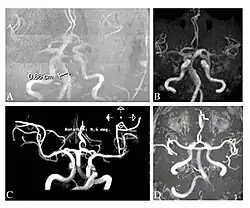

Die Prävalenz für einen Hirninfarkt liegt bei männlichen Patienten bei etwa 6,9 % und bei weiblichen bei 4,3 %. Sie ist wesentlich höher als in der Gesamtbevölkerung. Das mittlere Alter beim ersten Hirninfarkt beträgt bei Männern mit Morbus Fabry etwa 39 und bei Frauen 46 Jahre. Nicht selten ist ein Hirninfarkt die erste Manifestation des Morbus Fabry.[98] In den meisten Fällen wird der Hirninfarkt durch kleine Blutgefäße ausgelöst. Daneben sind noch Dolichoektasien (syn. dilatative Arteriopathien, Arterienaufweitungen) der vertebrobasilären Zirkulation als Auslöser beschrieben.[7][99][102] Die Thrombenbildung wird möglicherweise durch eine gesteigerte Adhäsion von neutrophilen Granulozyten und Monozyten an den Endothelien[103] oder durch eine lokal erhöhte Durchblutung (Hyperperfusion) gefördert.[104][105][106] Der Serumspiegel des Enzyms Myeloperoxidase ist bei Männern mit Morbus Fabry ein Biomarker für das Risiko eines vaskulopathisch bedingten Vorfalls.[7][107]

-

Die T1-gewichteten sagittalen (A) und axialen (B) MRTs zeigen ein symmetrisch hohes Signal im Thalamus (das sogenannte Pulvinar Sign) eines 66-jährigen männlichen Patienten. (C) und (D), ebenfalls T1-gewichtet, zeigen das Pulvinar Sign bei einem 42-jährigen Patienten. -

Die Time-of-Flight-Magnetresonanzangiographien von vier Morbus-Fabry-Patienten zeigen erweiterte (ekstatische) Blutgefäße (Dolichoektasien der vertebrobasilären Zirkulation).